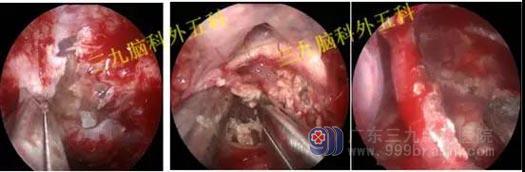

手术过程:完善相关检查后行内镜经鼻蝶鞍区Rathke’s囊肿切除术,通过微创全切囊肿。

手术过程:患者今日在全麻下行内镜经鼻蝶鞍区垂体腺瘤切除术,术中肿瘤全切,垂体保护良好。

手术过程:内镜下经鼻蝶鞍区垂体大腺瘤切除术,术中磨除鞍底,先行瘤内减压,双吸引器有序切除肿瘤,垂体及鞍隔保护良好,无脑脊液漏形成,肿瘤全切。

手术过程:内镜下经鼻蝶鞍区rathke囊肿切除术,术中打开鞍底,保护正常垂体,在下方最薄弱上台垂体,可见胶冻样囊液,给予全切,术中垂体、鞍膈保护良好,无脑脊液漏形成。

手术过程:内镜下扩大经鼻蝶入路,行鞍上区颅咽管瘤切除术+颅底重建术,术中肿瘤切除,垂体及垂体柄、视神经及视交叉、双侧颈内动脉保护良好,腹部脂肪及鼻中隔粘膜瓣修补鞍底。

手术过程:完善相关检查后行内镜经鼻蝶鞍区囊变垂体瘤切除术,肿瘤位于周边,囊液淡黄色位于中间,切除前部肿瘤,囊液流出,再行周围有序切除肿瘤,肿瘤全切,正常垂体及鞍隔保护良好,无脑脊液漏。

手术过程:内镜下经鼻蝶垂体瘤及rathke囊肿切除术,术中先行垂体腺瘤切除术,全切肿瘤后再行rathke囊肿切除,术中垂体瘤及囊肿全切,垂体主要位于右侧,保护良好。

手术过程:内镜下经鼻蝶鞍区垂体腺瘤切除术,磨除鞍底,剪开硬膜,有序切除肿瘤,肿瘤全切,鞍隔轻微脑脊液漏形成,腹部脂肪及鼻中隔粘膜瓣修复鞍底,球囊支撑鞍底。

手术过程:内镜下经鼻蝶垂体腺瘤切除术,垂体位于左侧,质地硬,沿着肿瘤包膜全切肿瘤

手术过程:内镜下经鼻蝶垂体腺瘤切除术,术中磨除鞍底,有序切除肿瘤,质地硬,沿着肿瘤包膜全切肿瘤,垂体位于左侧,术中垂体保护完整,无海绵窦侵犯。